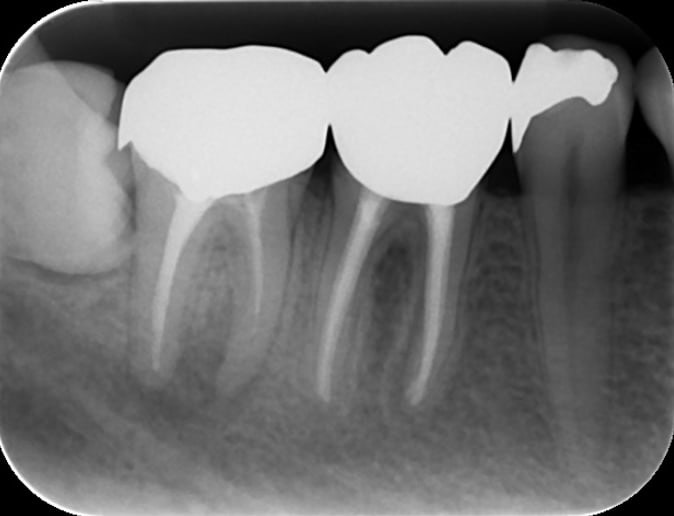

根管治療(初回の神経の治療)

術前

術後

初回の根管治療の成功率は比較的高く細菌感染レベルが低い場合は適切に治療すればGP(一般歯科医)でも成功する可能性は高いと思われます。ただし、術者の歯内療法におけるトレーニングの習熟度により成功率にばらつきが出ます。

日本全国で行われている一般的な根管治療の成功率は50%以下と推測されます。(日歯内療誌 32(1): 1~10, 2011より私的解釈)